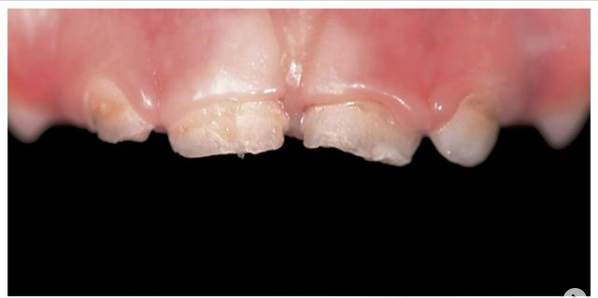

Бутина Елена Александровна: портфолио (8)